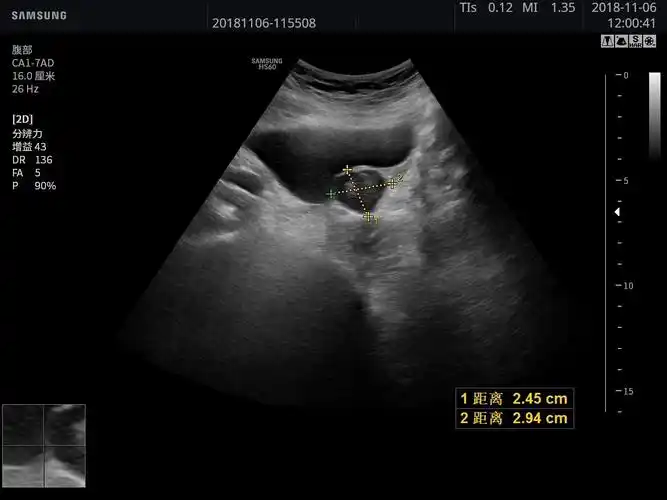

膀胱内实性占位,考虑为膀胱癌 - 超声医学讨论版 - 爱爱医医学论坛

超声图像显示于膀胱壁可见一偏低回声肿物,形态规则,边界清,cdfi示内